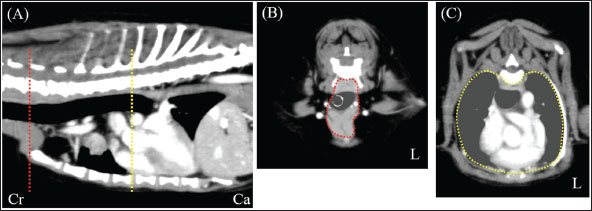

A neutered 9-year-old male Papillon weighing 3.5 kg was referred to the Okayama University of Science Veterinary Medical Teaching Hospital for examination and treatment of an incidentally discovered mass in the cranial intrathoracic cavity during regular medical checkups. The dog had no clinical signs and was in good general condition. However, a mass in the cranial thoracic region was detected by chest radiography. Blood tests showed no hypercalcemia, and arterial blood gas analysis showed no problems (Table 1). Polycythemia, slight hypernatremia, and hyperchloremia, which may be related to dehydration, were also observed. A chest X-ray revealed a mass of approximately 20 mm in the cranial intrathoracic cavity and mild expansion of the mediastinum (Fig. 1). The tumor-associated syndromes, such as megaesophagus and myasthenia gravis, were not observed. Computed tomography (CT) was performed under general anesthesia (Aquilion Lightning; Canon Medical Systems Co., Tokyo, Japan). Iopamidol (Oypalomin 300, Fuji Pharma, Japan) was used as a contrast medium (injection volume, 2.5 ml/kg [750 mgI/kg]; injection time, 15 seconds). Precontrast, arterial phase, venous phase, and equilibrium phase scans were obtained. The cranial intrathoracic mass (length, width, and height of 18.3, 16.0, and 18.6 mm, respectively) was a solitary lesion within the cranial mediastinum (Fig. 2). The mass was well demarcated, and there was no evidence of invasion into the surrounding blood vessels. The CT values of the mass were 43.2, 50.6, 113.1, and 102.2 HU for the precontrast, arterial, venous, and equilibrium phases, respectively (Fig. 2). These contrast enhancement effects were a preliminary diagnosis that the mass was a thymoma (Von Stade et al., 2019). Enlarged surrounding lymph nodes or distant metastasis were not detected. Due to the small size of the mass and its absence from the thoracic cavity margin, preoperative pathological examination could not be performed. Based on the CT results, the mass was provisionally diagnosed as a thymoma. The thymoma volume was measured from the length, width, and height by computed tomography using the elliptical volume formula. The cranial intrathoracic volume was measured using a 3D image analysis software (Ahmics-VAZE, PetCommunications Co., Ltd., Osaka, Japan). The cranial intrathoracic region between the first and fourth sternum at the beginning of the cranial intrathoracic cavity was assumed to be the surgical space for VATS-T (Fig. 3). The dorsal cephalic end was designated as the point where the first sternum extends perpendicularly and joins the thoracic vertebrae, and the dorsal caudal end was designated as the point where the fourth sternum extends perpendicularly and joins the thoracic vertebrae. This region was extracted and its volume was measured using the 3D volume rendering function by Ahmics-VAZE. The ratio of thymoma volume to cranial intrathoracic volume (T/CI ratio) was calculated as follows: thymoma volume/cranial intrathoracic volume × 100). The thymoma volume was 2.3 cm3, the cranial intrathoracic volume was 97.7 cm3, and the T/CI ratio was 2.4%. The thymoma volume was calculated using the approach in a previous report of two cases that described the thoracoscopic resection of thymomas (Mayhew and Friedberg, 2008). We also calculated the cranial intrathoracic volume for the dog, as it was of the same breed and weight as the two reported cases. Subsequently, we calculated the T/CI ratio. In previous reports, the thymoma volumes were 9.5 cm3 and 36.6 cm3, respectively, and the cranial intrathoracic volume was 892.8 cm3. The T/CI ratios were 1.1% and 4.1%, respectively.

Fig. 1. Chest X-ray imaging. (A) Right lateral view. (B) Ventrodorsal view. X-ray image: a tumor-like lesion measuring approximately 20 mm was observed on the cranial side of the heart (white arrow) (L): Left side.